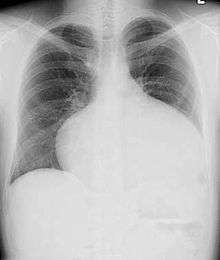

Most individuals with a significant ASD are diagnosed in utero or in early childhood with the use of ultrasonography or auscultation of the heart sounds during physical examination.

Some individuals with an ASD have surgical correction of their ASD during childhood. The development of signs and symptoms due to an ASD are related to the size of the intracardiac shunt. Individuals with a larger shunt tend to present with symptoms at a younger age.

Adults with an uncorrected ASD present with symptoms of dyspnea on exertion (shortness of breath with minimal exercise), congestive heart failure, or cerebrovascular accident (stroke). They may be noted on routine testing to have an abnormal chest X-ray or an abnormal ECG and may have atrial fibrillation. If the ASD causes a left-to-right shunt, the pulmonary vasculature in both lungs may appear dilated on chest X-ray, due to the increase in pulmonary blood flow.[40]